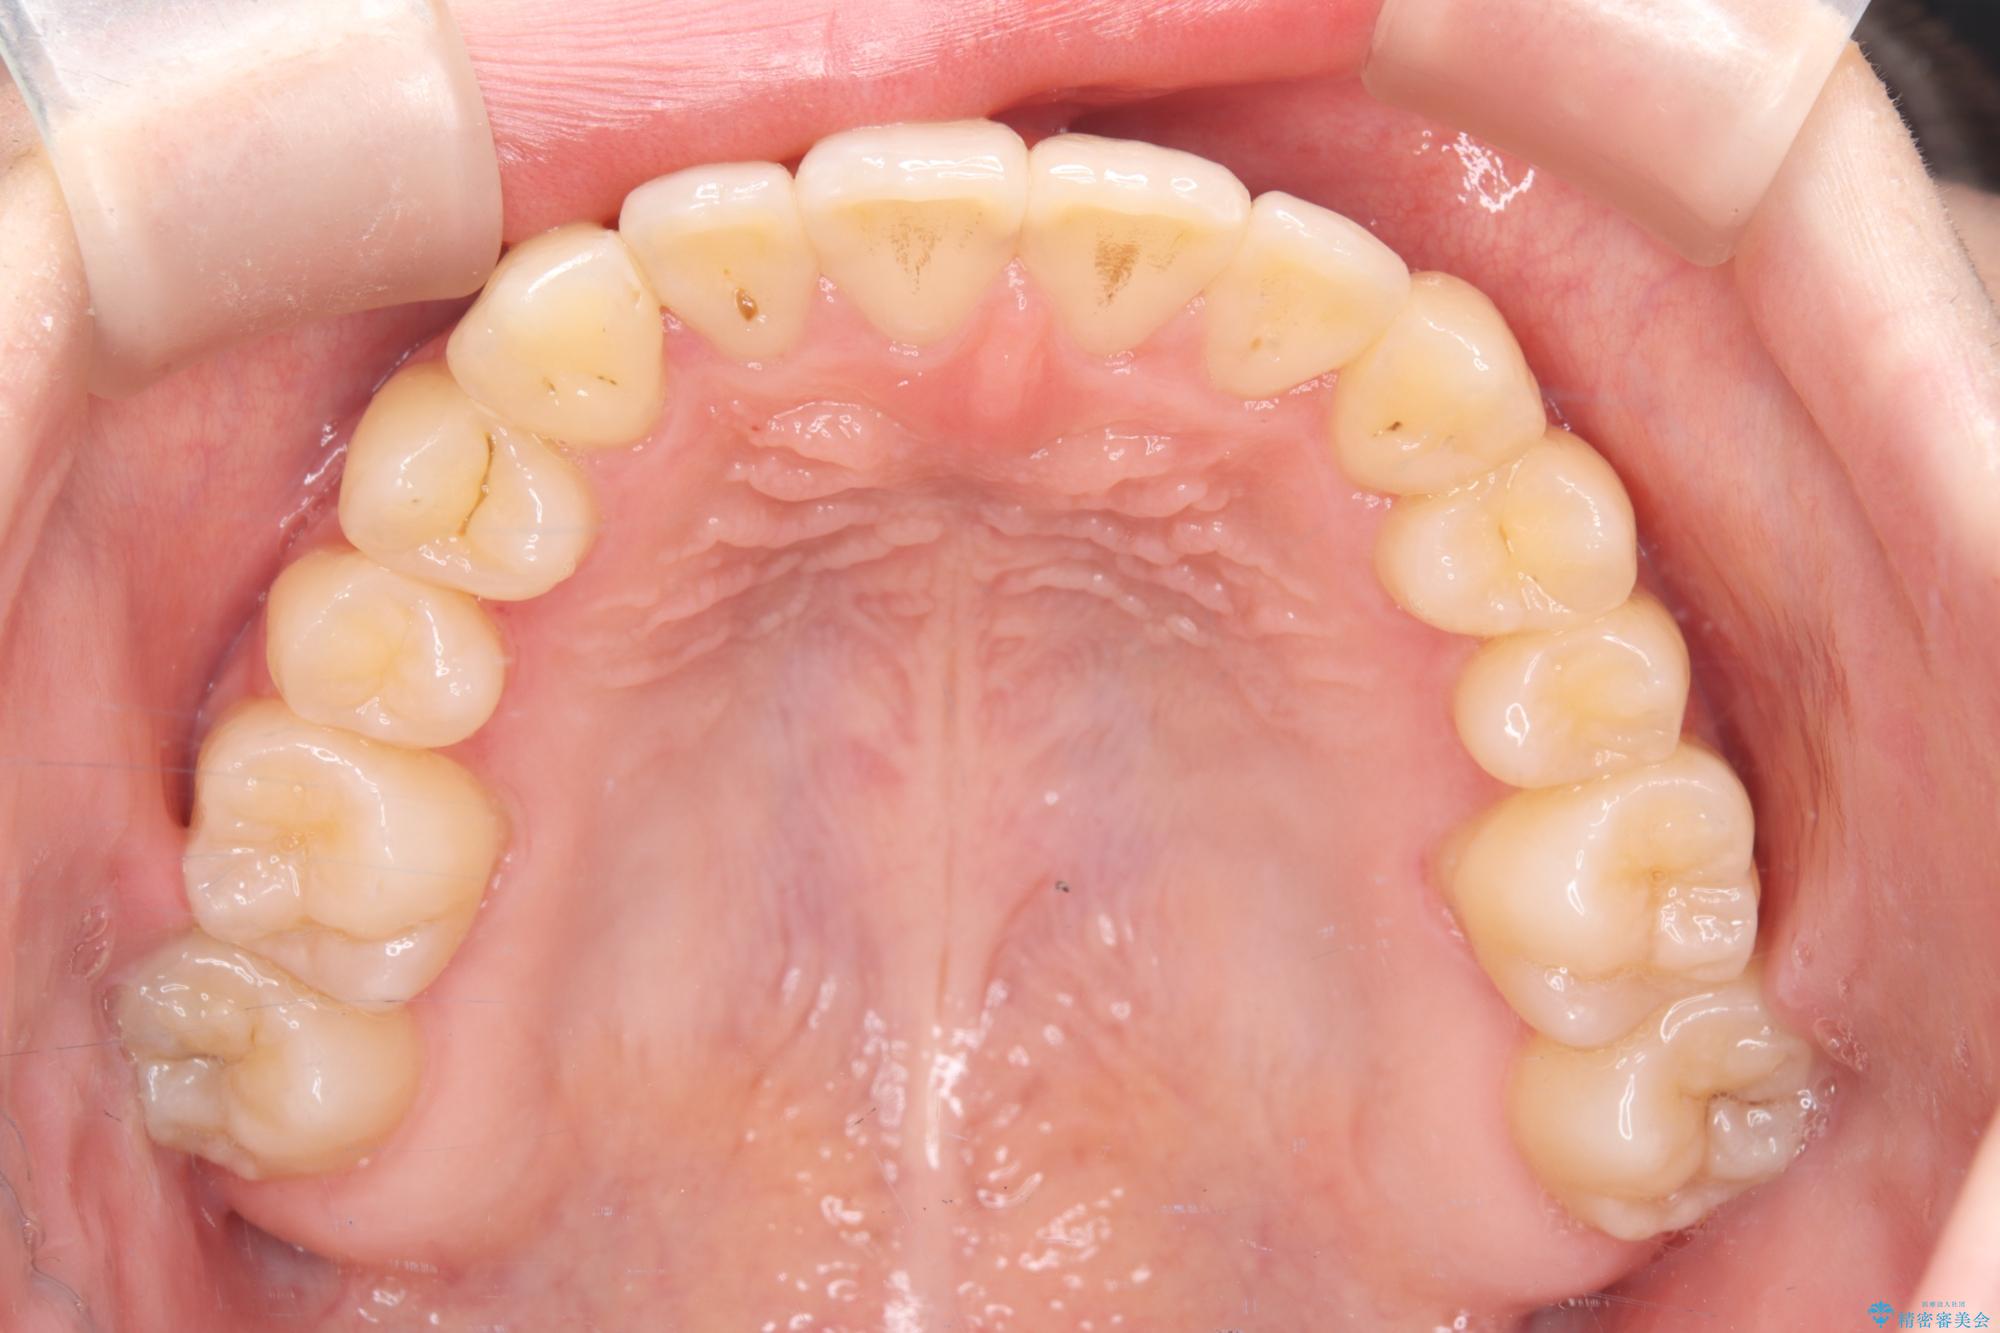

- 他院でインビザライン矯正を行っていたものの、通院先の閉院により治療が継続できなくなったとのことで来院されました。

診査の結果、すでに下顎前歯の抜歯が行われていましたが、マウスピースの適合が著しく悪くなっており、歯が計画通りに動いていない状態でした。また、歯を支える骨の厚みや歯肉の薄さを考慮すると、このままマウスピースによる傾斜移動を続けるのは歯肉退縮(歯茎が下がること)のリスクが非常に高いと判断。

安全かつ確実に抜歯スペースを閉じ、咬み合わせを完成させるため、マウスピースから**ワイヤー矯正(マルチブラケット装置)**へ切り替えるリカバリープランを提案しました。

転院という不安な状況にある患者様のストレスを最小限に抑えつつ、歯の健康を最優先にした処置を行いました。

装置の変更と歯肉への配慮: ワイヤー矯正は歯の根(歯根)を平行に移動させる「歯体移動」を得意としています。本症例では、歯肉退縮を防ぐために、歯の傾きを精密にコントロールしながら抜歯スペースを閉じる必要がありました。ワイヤー装置を用いることで、インビザラインでは難しくなっていた三次元的な細かい調整を可能にしました。